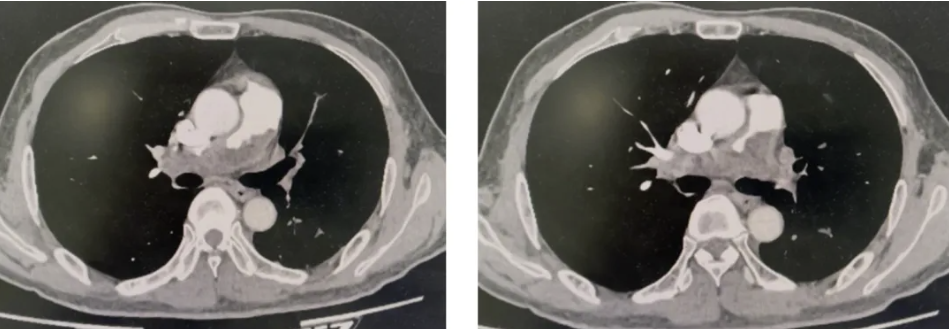

复查CTPA如下:

结合CTPA影像特征,高度怀疑肺动脉肉瘤,遂行右心导管+经导管肺动脉占位活检,活检病理提示肺动脉肉瘤。

CT上需警惕为肺动脉肉瘤的征象包括:肺动脉主干或近端阻塞程度较重的充盈缺损;肺动脉管腔内膨胀性改变;充盈缺损病变表面可呈突起形或分叶状,内部表现为不均匀强化;病变逆向血流方向生长,可表现为“反杯口征”;与血管壁连接紧密,可出现“蚀壁征”;部分可累及肺动脉瓣、心脏瓣膜及右心室流出道等周围结构。出现这些征象需警惕肺动脉肉瘤。